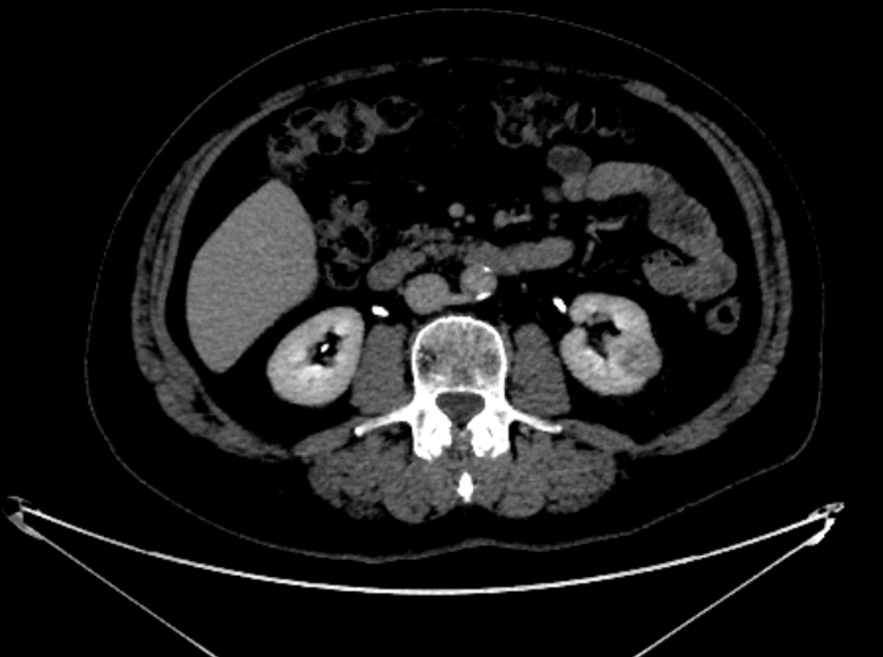

Tumeur du pole supérieur du rein gauche

Scanner abdominopelvien au temps tubulaire.